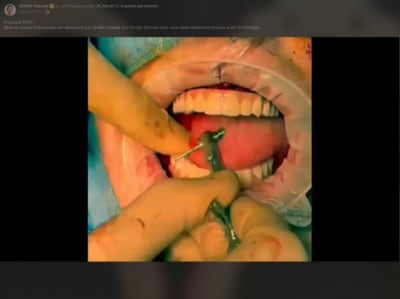

Tu es sur facebook, donc tu as peut être vu sa dernière vidéo ( sur son compte et sur le groupe workflow ).

Sinon : quelques capture d’écran .

Je crois que la, il n’y a plus de doute . Full zircone avec rosenscrew, pas de tibase .

J’ai pas mal de remodelage gingival qui m’empêcherai d’être en prothèse immédiate définitive ( avec des guillemets à « définitif », si tu veux ) . Il utilise une technique de suture suspendue qui évite peut être ce problème . La question sera à poser .

Le principal argument de la mise en en charge immédiate est de pouvoir proposer au patient un temps réduit au maximum pour avoir une prothèse esthétique et fonctionnelle. Les patients qui réunissent le besoin et les moyens sont peu nombreux. Souvent actif, ils veulent pouvoir retrouver une présentation correcte pour reprendre leur travail sans perte de temps. A 6 jours post opératoire comment tu trouves l'aspect esthétique du cas de Dimitri PASCUAL? jeff

.

Tu peux profiter de cette photo pour lire que le bridge n'est pas passif.